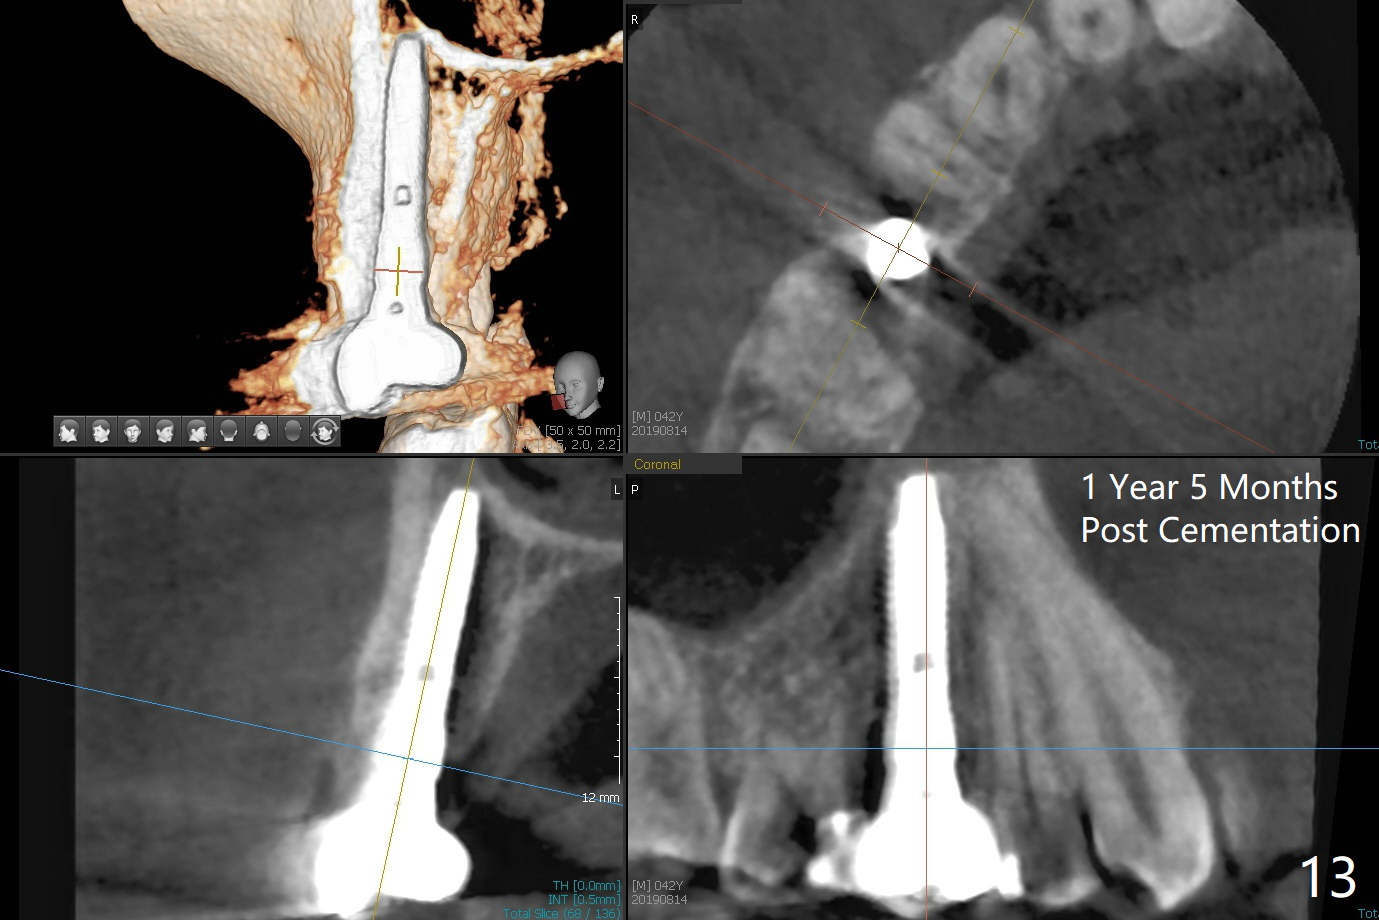

In fact there is a small buccal fistula, which is communicated with the underlying implant threads. Although preop CT shows that the buccal crest is lower than the palatal (3.8x13 mm, Fig.10 P) one, intraop finding of missing buccal plate should dictate a shorter implant (Fig.11) or onlay graft to avoid periimplantitis. Regeneration of the bone plate is limited. Later the fistula disappears with formation of a concavity (Fig.13). There is no symptom. Is bone graft necessary with a remote incision? 3-D images of CT taken 1 year 5 months post cementation show possible mesiobuccal and distopalatal bony defects (Fig.13-16). It is possible that bone graft was placed enough palatal (Fig.16). DO composite at #3 is redo satisfactorily (Fig.17 *).